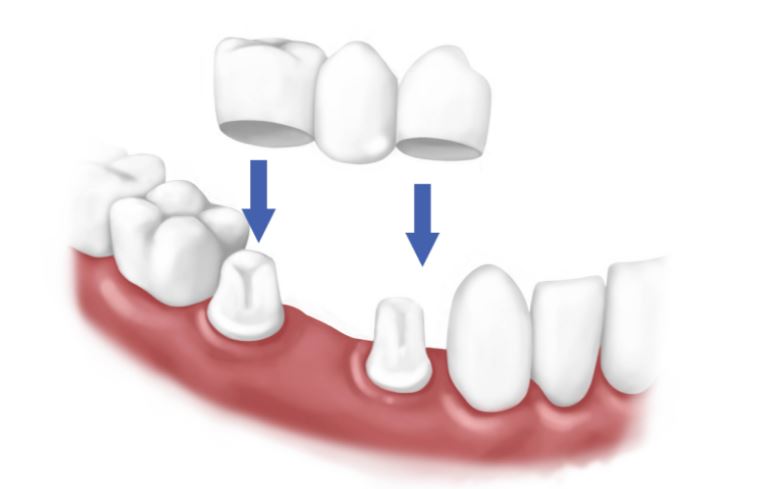

طرق تلبيس الاسنان في تركيا

من الضروي أن يعرف المريض ما هي طرق تلبيس الأسنان والمراحل التي سيمر بها قبل عملية تلبيس الأسنان وبعدها.

مراحل عملية تلبيس الأسنان في تركيا :

قبل عملية تلبيس الأسنان يجب أن يتعرف الطبيب على مشكلة الأسنان عن قرب، فعند مراسلة المركز الطبيب يرسل المريض صورة شعاعية للأسنان حتى يتمكن الطبيب من التعرف بشكلٍ مبدأي على المشكلة، وعند وصول المريض للمركز الطبي فإنه يمر بعدة مراحل تنتهي بتلبيس الأسنان والتأكد من ثبات التيجان، وتتمثل تلك المراحل فما يلي:

مرحلة الفحص: وفيها يكون فحص الأسنان مباشر، فيقوم الطبيب بالكشف وعمل أشعة سينية إذا تطلب الأمر، ثم يحدد المشكلة التي تعاني منها الأسنان ليبدأ بعلاجها قبل تلبيس الأسنان.

مرحلة العلاج: عند وجود مشكلة تسوس بالأسنان، أو تضرر عصب السن فإن الطيب يقوم بتنظيف الأسنان أولاً والتخلص من العصب المتضرر حتى لا يسبب ألم بعد تلبيس الأسنان، وبعد الانتهاء من تنظيفها وعلاجها يتم تركيب تيجان مؤقتة لحفظ الأسنان حتى تركيب التيجان النهائية.

مرحلة أخذ القياسات: حيث يبدأ الطبيب في استخدام قوالب خاصة بأخذ قياسات الأسنان، ويبدأ في نحت الأسنان وتجهيزها لأخذ القياس، ومن ثَم يضع عليها القالب ليأخذ شكل وحجم الأسنان بعد تجهيزها، ويتم إرسال القالب للمخبر المختص بتصنيع تيجان الأسنان.

مرحلة تلبيس الأسنان: وهي المرحلة النهائية التي يضع فيها الطبيب بتيجان الأسنان، ويقوم الطبيب بتنظيف الأسنان وشطفها جيداً وتجفيفها تماماً قبل تلبيس التيجان، ثم يتم تخدير مكان التلبيس تخديراً عادياً كالمتعارف عليه في عيادات الأسنان حتى لا يشعر المريض بأي ألم، ويضع الطبيب المادة اللاصقة وعليها التيجان ويتأكد من مناسبتها لشكل الأسنان قبل تثبيتها، وبعد التثبيت يتأكد مرة أخرى أن حجمها مناسب ولا تحتاج لأي تعديل.

تلبيس الاسنان الاماميه بالصور

وسنتعرف في هذه الفقرة على طريقة تلبيس الأسنان الأمامية وصنع التاج مرفقة مع بعض الصور لتوضيح التغيير الشامل الذي يظهر على الفم.

إن تلبيس الاسنان الاماميه بالزركون تتم من خلال زيارتين لطبيب الأسنان كالآتي:

خلال الزيارة الأولى يفحص الطبيب أسنان المريض ويقوم بتحديد التلف الذي بالأسنان، ويقوم بدراسة الأسنان بدقة، والعمل على تحضيرها بشكل طبي. يحرص الطبيب على عمل طبعة خاصة بالأسنان، ويتم أخذها للمختبر من أجل صُنع التاج الخاص بها، وهذه الخطوة مهمة من أجل معرفة الشكل الخاص بالأسنان بالإضافة إلى حجمها وأيضًا المسافة الخاصة بالتاج.

يضع الطبيب تاج مؤقت من أجل تغطية كافة الأسنان المكشوفة والتي قد تم حفرها، من أجل عدم حركتها إلى أن يأتي الموعد المُحدد لتركيب التاج. أما عن الزيارة الثانية للطبيب يقوم ببرد الأسنان بشكل طبي، ويتم أخذ طبعة بعد ذلك سواء اللثة أو الأسنان، بعد إجراء عملية البرد ويتم إرسالها للمختبر من أجل تصنيع التاج.تكلفة تلبيس الأسنان في تركيا

بعد ذلك يعمل الطبيب على إزالة التاج وتركيب التاج الآخر الدائم. إن استعمال التاج يدوم إلى 10 سنوات وذلك طبقًا للاهتمام به، ويتم تنظيف الأسنان بشكل دائم. تكلفة تلبيس الأسنان في تركيا